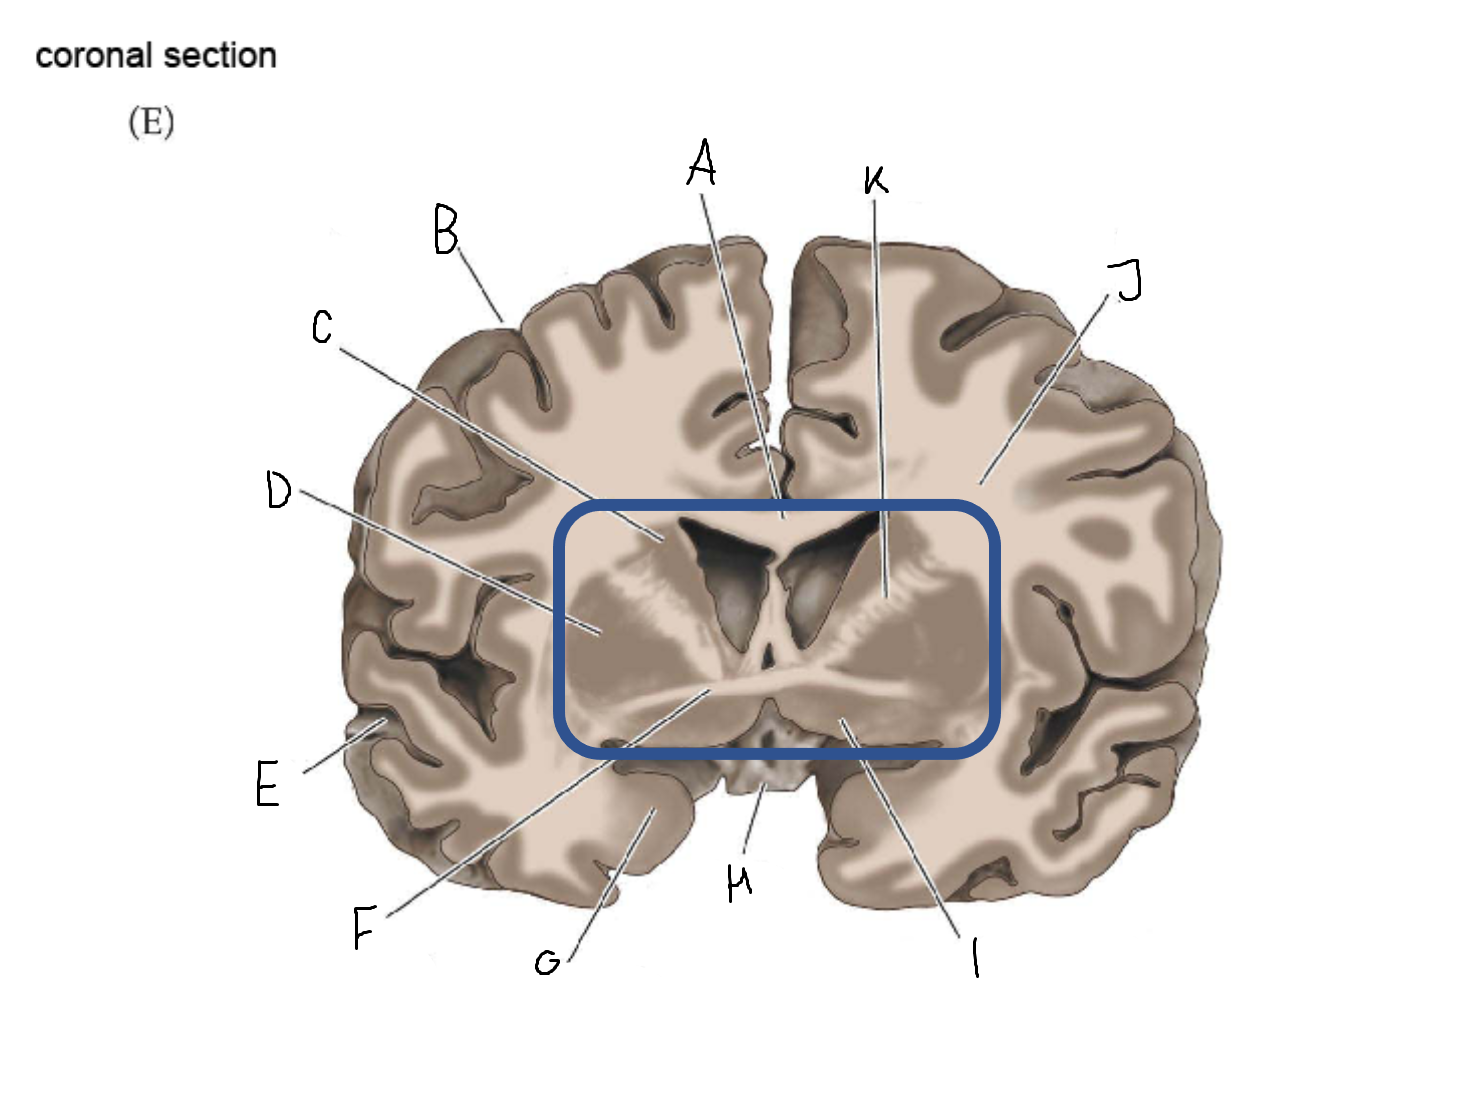

A

head of caudate nucleus

C

putamen

D

external segment of globus pallidus

E

internal segment of globus pallidus

F

third ventricle

G

thalamus